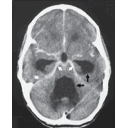

Méningite tuberculeuse.png